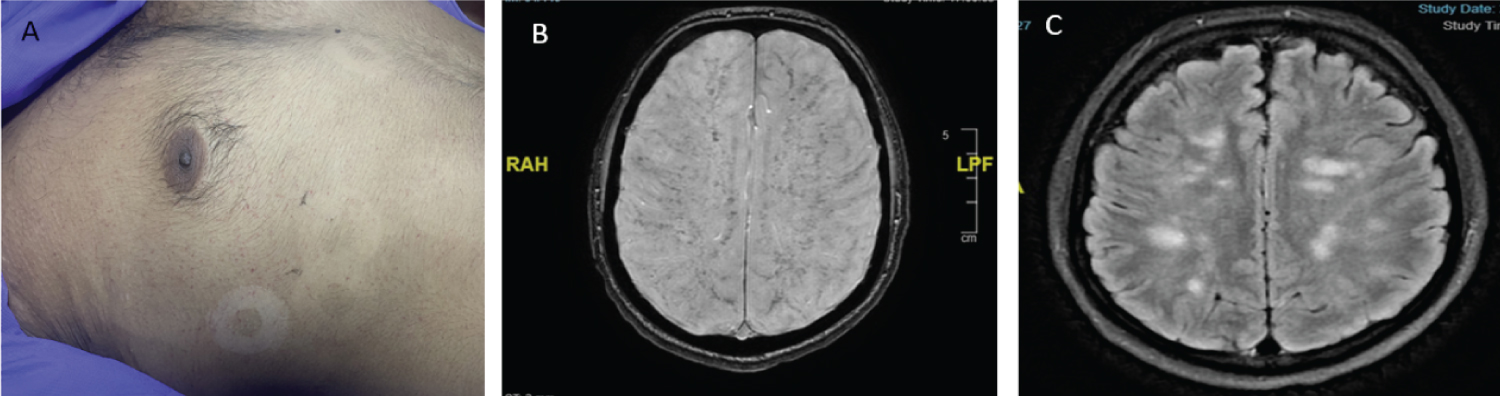

A 33-year-old man admitted to the emergency department after being involved in road traffic accident. On evaluation and radiological imaging, he sustained closed subtrochanteric fracture in the right femur and a bilateral pelvic. Following primary survey and initial resuscitation, the patient was haemodynamically stable, so the patients shifted to a ward for further management. After 24 hours, the patient exhibited changes in mental status, including drowsiness, confusion, and restlessness with presence of petechial rash (Figure 1A). Additionally, he experienced respiratory distress and hypoxia on arterial blood gas analysis. He was promptly shifted to the trauma intensive care unit (ICU) where tracheal intubation was performed. His urinalysis was normal. On Radiological imaging, including chest X-ray and CECT chest, did not reveal any abnormalities. But MRI brain showed multiple small lesions scattered throughout the deep white matter of the brain on FLAIR imaging (Figure 1B) and multiple small infarcts with a characteristic "starfield pattern" in susceptibility-weighted imaging (Figure 1C). Supportive treatment continued and after three days, the patient was successfully extubated. Five days later, he underwent uneventful surgery for proximal femur nailing and finally discharge. A diagnosis of cerebral fat embolism syndrome was made on the classic clinical triad of hypoxemia, neurological abnormalities, and a petechial rash along with classical MRI brain finding. Treatment primarily involves providing supportive care with surgical correction. In severe cases, symptoms may persist for several days, but most patients ultimately achieve complete recovery [1-5].

Figure 1: (A) Showing petechial rash in chest area; (B) MRI (T2 Swan sequence): Showing Diffuse microhemorrhages involving white and grey matter (Walnut kernel microbleed pattern); (C) MRI (T2 Flair sequence): Multiple Hyperintense Lesion (Starfield appearance).